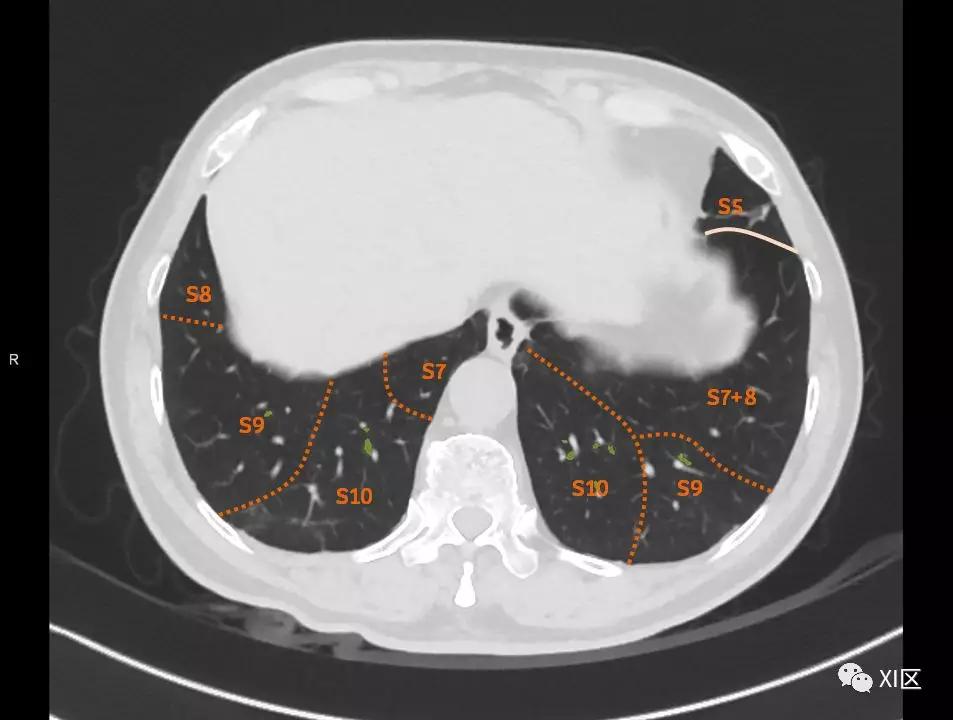

肺的断层分段示意图

在进行肺的分段时,可以上下观察浏览,沿着相应气管的走形可以更容易准确地进行分段。